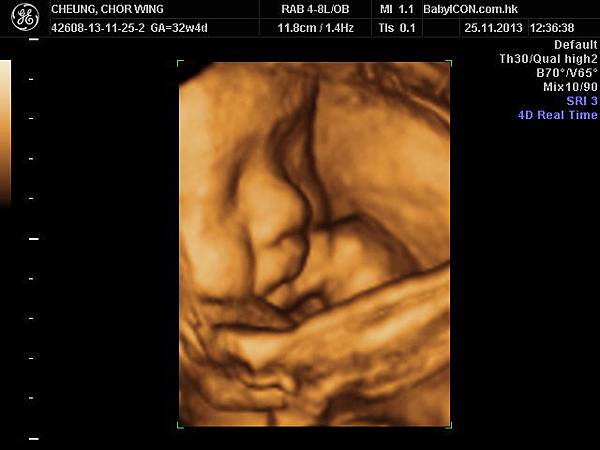

另外我除了每個月都會去CHECK和照超星波外

我還去過BABY ICON照4D

我之前也打過一篇介紹

連我自己都話照4D很浪費錢

因為是非醫學的

只是想看看BB而已

不過我最後還是也跟去照了

我好像30週後才照的,我也不記得了

就是11月25日照麻

我認為後期D照會清好多呢

我也很幸運的,LUCAS BB做左好多動作表情啊

偷笑^^

很好的一個體驗